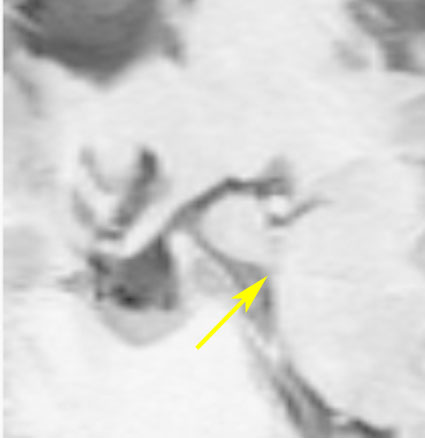

2歳でgelastic seizureを発症,6歳で思春期早発となりました

左視床下部に限局して柄を有するものです,左視索と乳頭体との境界はありません

おそらく左視床下部の機能低下と難治性の発作が原因で,左大脳半球の萎縮(あるいは発達不良)が認められます

予後がかなり不良だと判断して,2004年に摘出術をしました

術後のMRIです,pterional approach でしか摘出できない腫瘍でした

高い位置がとどかず少し取り残しました

gelastic seizureは減荷されましたが残り,術後に視野欠損を後遺しました

2019年時点でもこのよう過誤腫を治療することは困難です